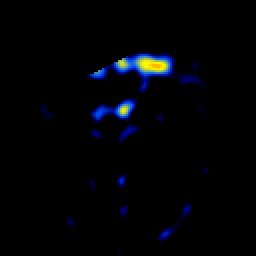

glioma overlay -- Slice #9

[Home][Help][Clinical] Slice 9